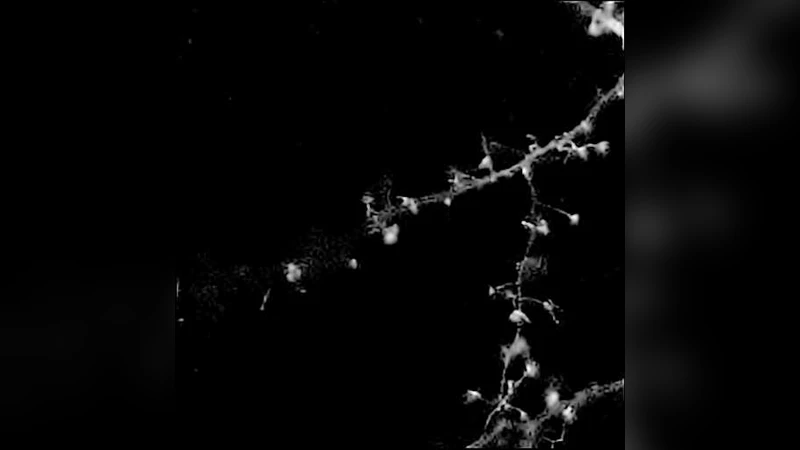

실험에서는 신경세포와 혈관 내피세포의 시뮬레이션 데이터 및 실제 공초점 이미지에 대해 RL‑TV, RL‑MRS, NaiveGauss, AnsGauss 등 네 가지 기존 방법과 비교하였다. 저강도(최대 30) 상황에서 제안법은 ℓ₁‑오차와 MSE 모두에서 RL‑MRS와 동등하거나 더 낮은 값을 기록했으며, 시각적으로도 배경 잡음 억제와 구조 보존이 뛰어났다. 중·고강도에서는 RL‑TV가 일부 세부를 강조하지만, 제안법 역시 경쟁력 있는 복원을 제공한다. 연산 시간 측면에서는 MATLAB 구현 기준 2.7 s(제안법)로, C++ 기반 RL‑MRS(15 s)보다 현저히 빠르다.